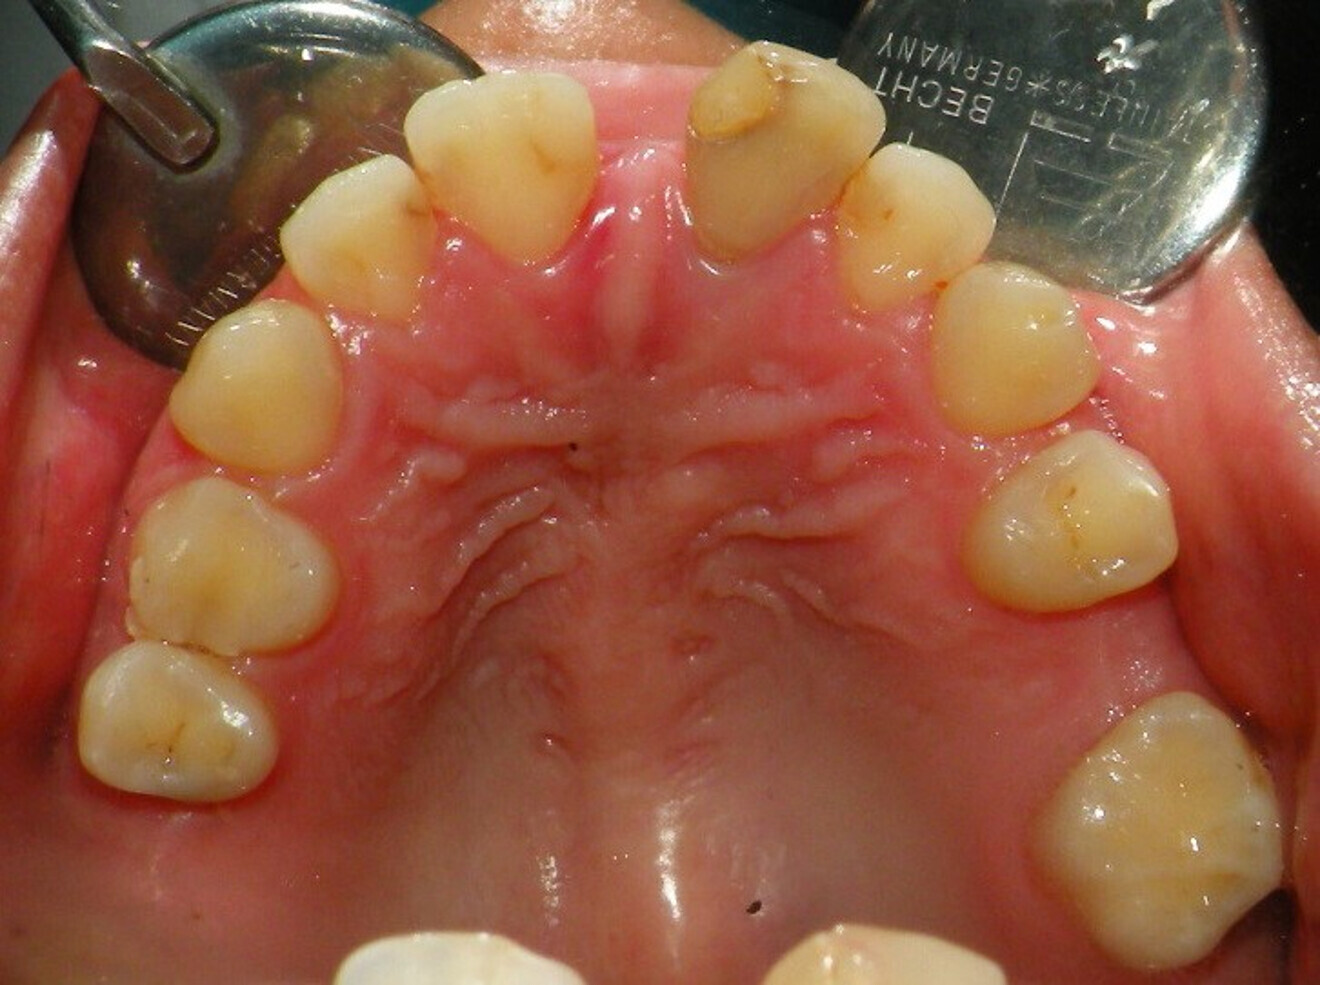

Case 2

• 50-year-old woman

• No underlying medical condition.

• Main complaint: Multiple gaps.

Intra-oral findings:

Class I malocclusion with poli diastemas in both upper and lower arch.

Overbite= 1mm Overjet = 3mm

No molar classification (absence of molars)

Class I canine on right and left side.

Upper midline (mesial to 11) on with face.

Lower midline on with the chin.